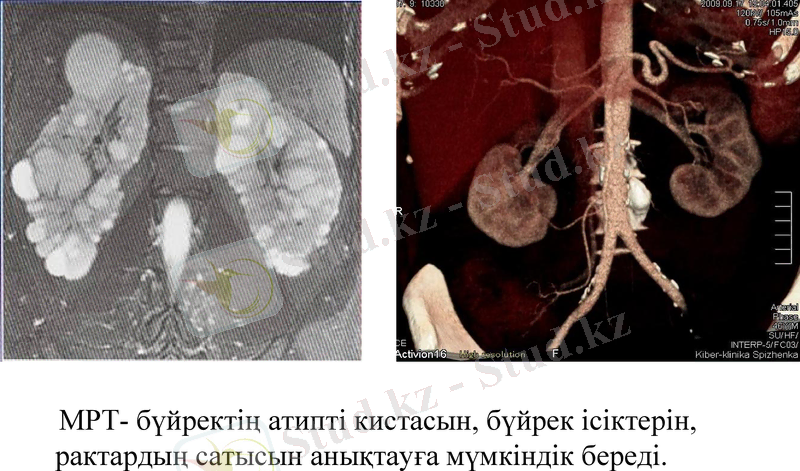

МРТ- бүйректің атипті кистасын, бүйрек ісіктерін, рактардың сатысын анықтауға мүмкіндік береді.